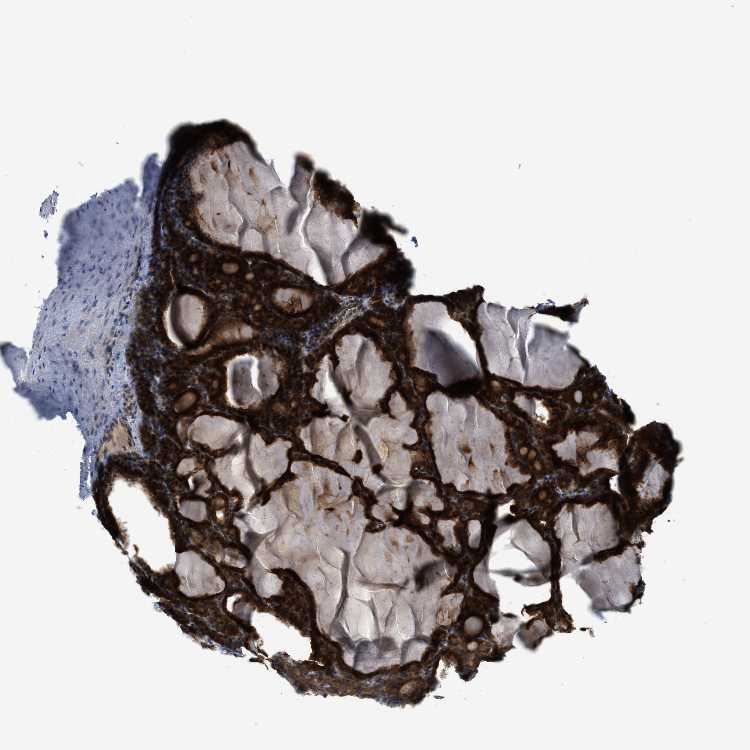

THYROID GLAND - Antibody stainingi

Antibody staining in the annotated cell types in the current human tissue is reported as not detected, low, medium, or high, based on conventional immunohistochemistry profiling in selected tissues. This score is based on the combination of the staining intensity and fraction of stained cells.

Each image is clickable and will lead to virtual microscopy that enables deeper exploration of all samples and also displays staining intensity scores, fraction scores and subcellular localization as well as patient and tissue information for each sample.

Antibody HPA018002Antibody HPA024071Antibody CAB013470

Glandular cells HighMediumMedium